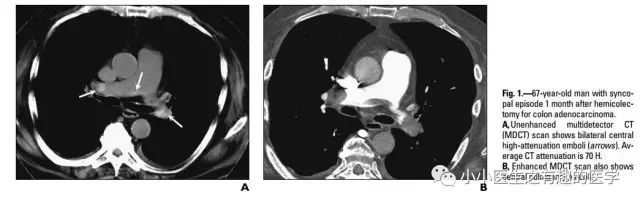

另外,CT发现肺纹理减少,也要警惕肺栓塞。先来说说马赛克。

马赛克征象:由于气道疾病或肺血管性疾病,引起相邻的肺区血液灌注上的差别而出现的不均匀肺密度区,称马赛克灌注。

以图说话,下面都是马赛克,关注了

假如CT平扫发现肺部某些地方血管稀疏,灌注不够,千万不要以为没事,有时候,就是肺栓塞,需要警惕。

马赛克,需要警惕肺栓塞,它是肺栓塞的间接表现。并且,在临床中,间断会遇到这样的情况。